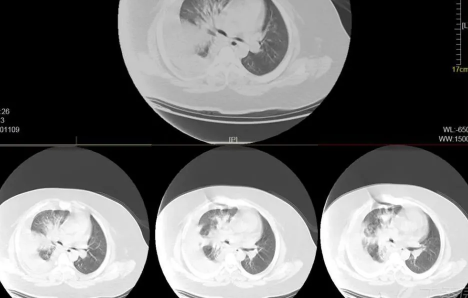

如果出现白肺,患者可能会出现一些严重的呼吸道症状,包括咳嗽、喘息、呼吸困难或体力活动时呼吸短促。一个更客观的指标是病人的呼吸频率,通常大于每分钟30次呼吸,或血氧饱和度低于93%就要警惕出现严重肺部感染。白肺并不能预防,只能预警。

肺白了一般是指白肺,白肺能否恢复与疾病类型、严重程度有一定关系,有些患者在检查时,发现肺白密度增高,如果是轻度肺部炎症引起的白肺一般是可以恢复的,如果是严重肺部炎症或肺间质纤维化引起的,则可能无法恢复。

如果是比较严重的肺炎或肺间质纤维化引起的白肺,一般会伴有呼吸困难的症状,首先应该改善患者的呼吸状态,可以帮助患者通过吸氧呼吸,也应该使用抗生素类药物进行治疗,症状消退后,白肺症状会相应减轻,但一般不会完全恢复。